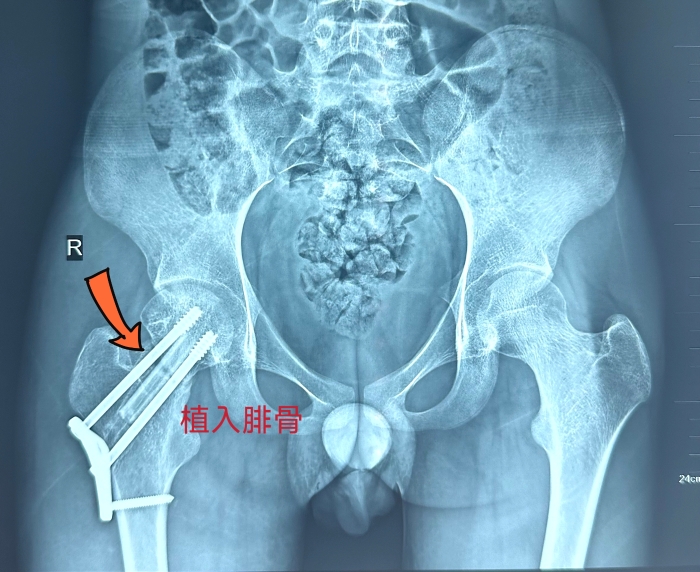

右/術(shù)後

姬傳磊向小吉和家屬充分(fēn)說(shuō)明了手術(shù)方案及愈後效果,取得(de)同意後,于近日(rì)行右側股骨頸骨折内固定裝置取除+取右側腓骨瓣移植、右股骨頸骨折切開複位内固定術(shù)。在團隊的密切協作(zuò)下,手術(shù)曆時4個小時順利完成。

姬傳磊介紹,在帶血管蒂遊離(lí)腓骨移植術(shù)中,切除腓骨不會對人(rén)體(tǐ)産生(shēng)明顯的不良影(yǐng)響,而且腓骨在骨重建中,不僅能起到重建血供的作(zuò)用,還(hái)能給股骨頭提供有活力的可(kě)靠血供,最終保留自(zì)體(tǐ)股骨頭,維持髋關節功能。